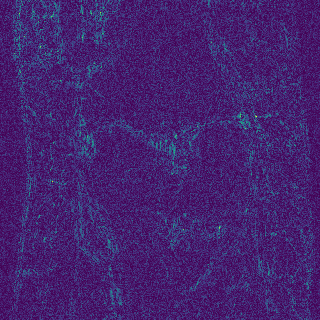

EPN is utilized to provide edge priors for later reconstruction, so the quality of the predicted edges is very important. In Fig. 10, we provide some qualitative results of the predicted edges of EPN on three multi-coil datasets. Among them, the GT edges are extracted using the Sobel operator. As can be seen from the images, our proposed EPN can predict an approximate contour for the overall subject and can reconstruct accurate edges close to the GT edges under two acceleration factors. This fully verifies the effectiveness and excellence of the proposed EPN.

Edge preserving has always been a crucial concern in the design of reconstruction models. To improve the quality of reconstructed images and preserve image edges, some works suggested introducing edge priors in the original restoration problem to preserve image edges [4, 34]. However, they will suffer from complicated algorithm design and time-consuming training processes. Recently, some more efficient methods have been proposed to use edge maps as external guidance for image restoration. For example, Yang et al. [48] used off-the-shelf edge detectors to extract image edges from the degraded images. Fang et al. [12] predicted image edges by constructing an edge reconstruction network. Huang et al. [18] designed a novel dual discriminator GAN framework for solving fast multi-channel MRI, in which one GAN network is built for edge information enhancement. Inspired by these methods, we also consider introducing image edge prior as external guidance to MRI reconstruction since 1) image edges are prominent and distinguishable features in MRI (see Fig. 1), which can serve as a good guide to the model to recover high-frequency details; 2) the ground truth edges can be easily fetched via ordinary edge extraction operators, like Canny, Sobel, and Prewitt, which means that the edge maps can be learned in a data-driven manner. However, how to effectively utilize image edge priors to guide image reconstruction still remains a challenge. In some methods, edge information was simply concatenated with the input image and passed to the next stages. Though this is a simple way to utilize the edge priors, it may not give full play to the guiding role of the edge priors. Therefore, in this work, we want to explore a more efficient and effective mechanism to fully take advantage of image edge priors.

fastMRI is a large-scale MR dataset jointly established by Facebook AI Research and NYU Langone Health. It provides both knee and brain datasets for evaluation. In our work, we use the multi-coil knee dataset, which was acquired on three clinical 3T systems or one clinical 1.5T system using a 15-channel knee coil array. The dataset includes data from two pulse sequences, yielding coronal proton-density weighting with (PDFS) and without (PD) fat suppression. As is shown in Fig. 1, PD images usually contain more structural and prominent edge features than PDFS images, which suggests that it is more challenging to use edge guidance on PDFS datasets. Therefore, we explore the effectiveness of EAMRI on these two modalities. Following [13], for both PD and PDFS knee datasets, we separately filter out 227 volumes (8332 slices) for training and 24 volumes (1665 slices) for testing. The dataset is centrally cropped to .